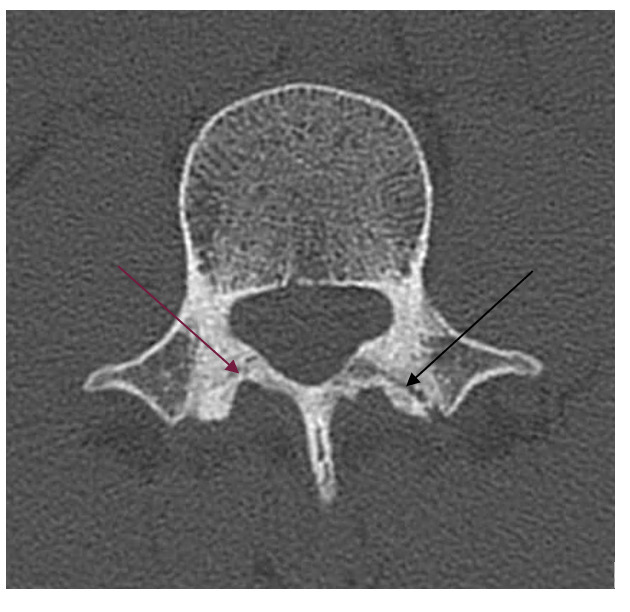

Les radiographies réalisées ne révèlent aucune anomalie (fig. 1). Le scanner demandé secondairement montre une lyse isthmique bilatérale en L3 prédominant à gauche (fig. 2).

Le diagnostic est celui d’une spondylolyse. La prise en charge a consisté en une immobilisation par corset ainsi qu’une surveillance clinique régulière jusqu’à disparition de la douleur.